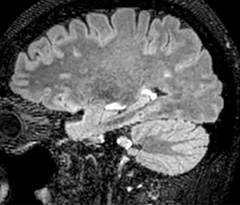

Fast MS protocol with optional sequences

The abbreviated MS protocol for brain is only around 9 minutes, so in case of suspected multiple sclerosis, one or two more advanced sequences may be added, such as PSIR (phase sensitive inversion recovery) or susceptibility-weighted sequences to help us make more confident diagnoses in these inflammatory cases.

In this example, the optional 3D multishot susceptibility weighted sequence with 0.6 mm isotropic voxels is 2 lesions with a central vein sign (arrows) and one lesion with a phase-rim sign (arrowhead). The total scan time, including SmartBrain and axial PD/T2 3mm, is 11:10 min. and is 18:30 min. with the optional 3D PSIR and 3D SWI multishot included.

3D TFE T1

3D FLAIR

DWI image

3D T1w TSE Gd

3D PSIR

3D SWI

“In multiple sclerosis patients, we increasingly include a multishot susceptibility sequence [3] in our routine cases, thanks to the shorter scan times. Our abbreviated MS protocol for brain is around 8 to 9 minutes, so we can ask for one or two additional sequences to visualize the central veins, or to get an additional contrast to better depict posterior fossa lesions. In cases of white matter lesions of unknown significance on FLAIR images, for example when we see high signal hyperintensities in the brain, we can add on more advanced sequences such as PSIR (phase sensitive inversion recovery) or susceptibility-weighted sequences to help us in distinguishing between MS and nonspecific or vascular abnormalities in these inflammatory cases.”